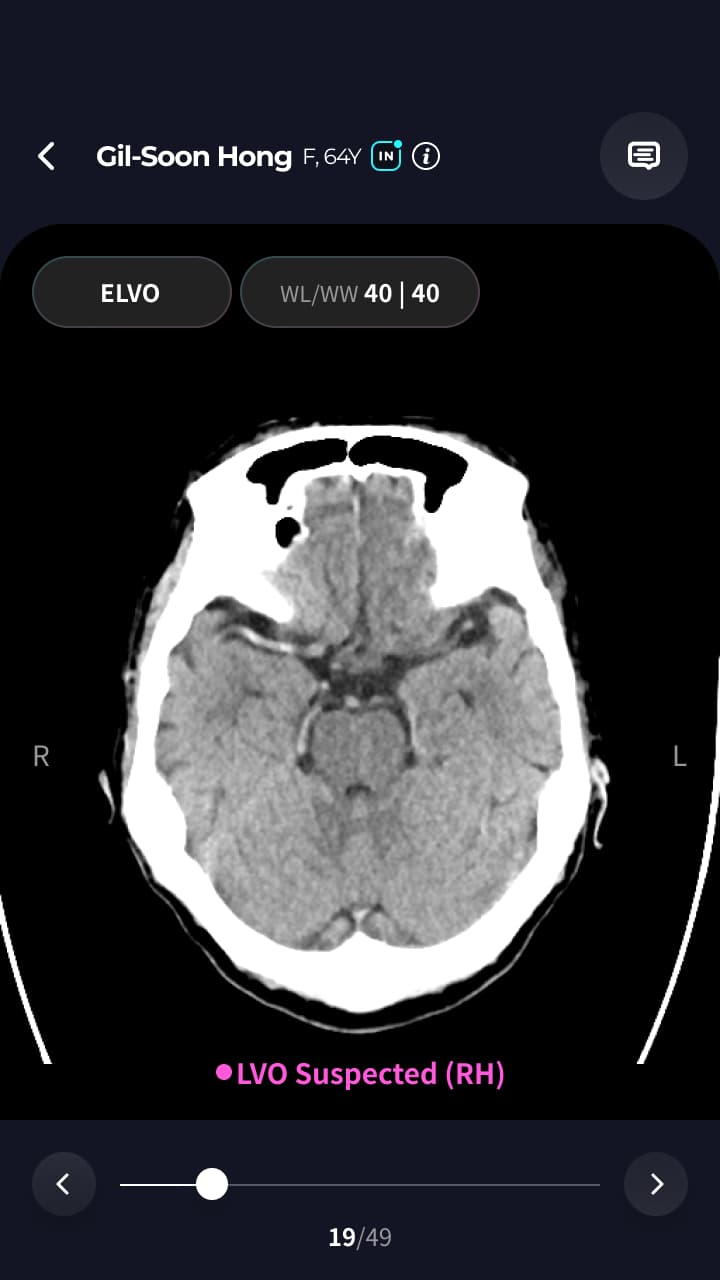

뇌졸중 신속 선별 AI 솔루션의 모바일 앱 개발 프로젝트입니다.

뇌졸중 신속 선별 AI 솔루션의 모바일 앱 개발 프로젝트입니다. WebView 연동, 채팅 기능, 알림 기능 등 핵심 기능 개발을 담당했습니다.

- WebView Bridge를 사용하여 DICOM 웹 모바일 화면 연동 개발

- WebView Bridge를 활용한 DICOM 의료 영상 웹 연동 구현